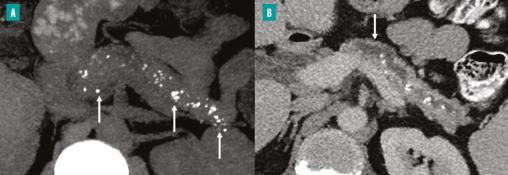

L’acquisition sans injection (A) montre la présence de multiples calcifications pancréatiques (flèches), de taille variable et distribuées de façon diffuse dans le parenchyme pancréatique ainsi que dans le conduit pancréatique principal. La TDM après injection de produit de contraste au temps portal (B) montre la présence d’un conduit pancréatique principal dilaté et irrégulier, sans véritable sténose. Une atrophie de la glande pancréatique, plus marquée au niveau de la jonction isthme-corps, est visible (flèche).